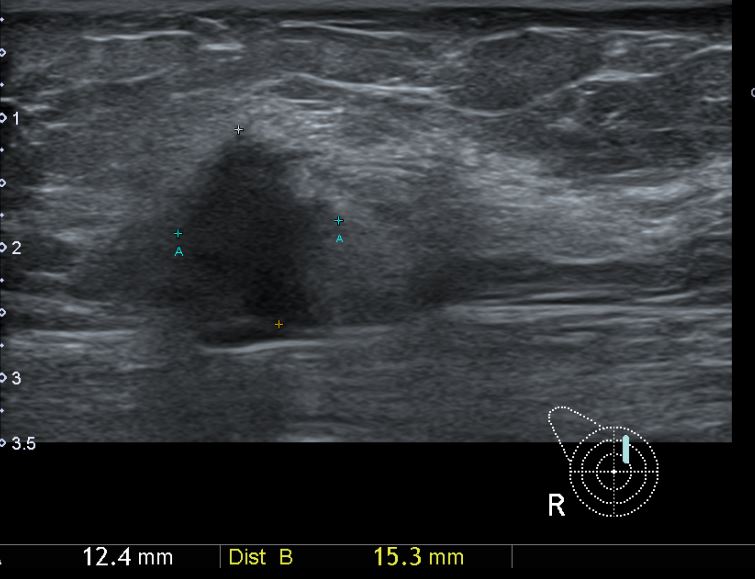

아산유외과 개원후 635번째 유방암진단

상기환자 외부검사상 이상소견으로 내원하신 50대여성으로 우측 유방의 의심스러혹

조직검사시행해 유방암 진단되었읍니다